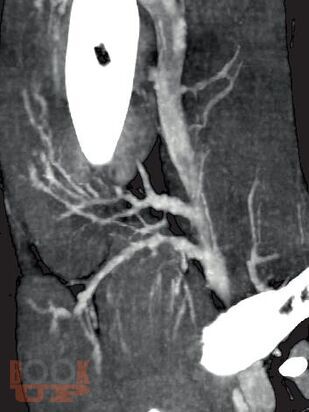

Современные методы диагностики заболеваний бассейна нижней полой вены

Учебное пособие содержит основные сведения о анатомии и физиологии венозной системы нижних конечностей, морфологии и патофизиологии данных заболеваний, современных методах диагностики. Рассчитано на ординаторов и слушателей ФДПО хирургических специальностей.